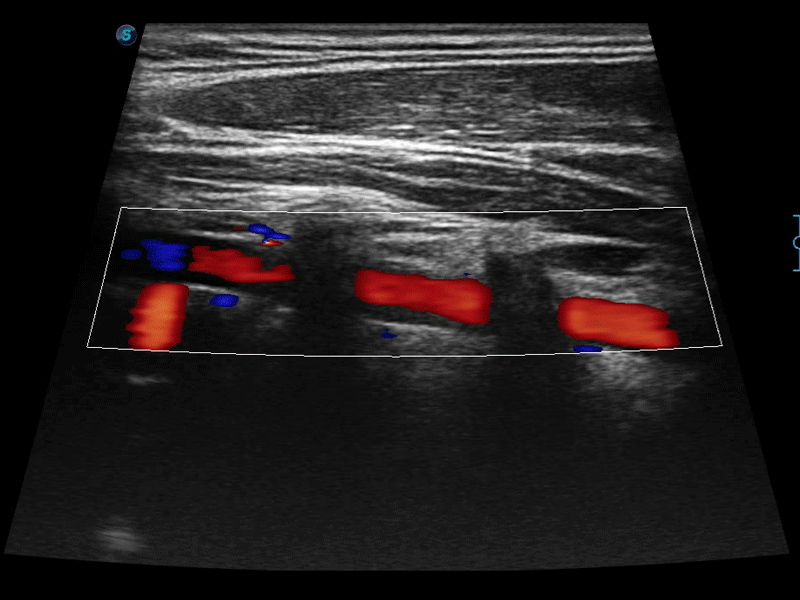

临床图像

• 实时宽景成像技术

通过色彩血流和实时宽景相结合,可观察到完整的静脉或动脉的血流,方便医生检查。实时扫查过程中,如有任何操作失误也可以很容易地进行回扫擦除,而不会中断扫查。